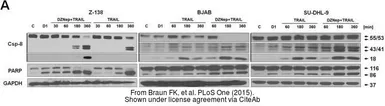

The data was published in the journal PLoS One in 2015. PMID: 25738497

The data was published in the journal PLoS One in 2015. PMID: 25811469

The data was published in the journal PLoS One in 2015. PMID: 25811469

The data was published in the journal PLoS One in 2015. PMID: 25928539

The data was published in the journal PLoS One in 2015. PMID: 25811469